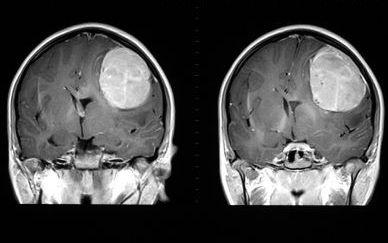

: 뇌종양이란 머리 안쪽, 다시 말해 두개강 내에서 발생하는 모든 종양을 일컫는 용어이고, 뇌세포와 이를 지지해주고 있는 세포들, 뇌에서 얼굴과 목 등을 조절하기 위해 뇌에서 직접 나오는 뇌신경, 뇌를 싸고 있는 뇌막, 호르몬을 분비하는 샘 등에서 모두 종양이 발생할 수 있습니다. 이렇게 두개강 내 자체에서 발생하는 종양을 원발성 뇌종양이라 부르고, 다른 기관에서 먼저 발생한 악성 종양(암)이 뇌로 전이된 경우도 있는데요, 이런 경우는 전이성 뇌종양이라 부릅니다.

양성 뇌종양의 경우에는 수술적 치료 후 별도의 추가 치료 없이 주기적으로 CT와 MRI 같은 영상을 촬영하며 경과를 관찰하는 것이 일반적입니다. 똑같이 개두술을 시행하더라도 그 접근법은 매우 다양합니다. 우리 뇌는 머리뼈에 둘러싸여 있고, 아래쪽으로는 눈, 코, 귀, 목 등이 위치하고 있기 때문에 모든 부분을 쉽게 노출하고 접근할 수 있는 것은 아닙니다. 그래서 뇌종양은 발생된 위치나 환자분이 현재 갖고 있는 증상의 종류와 심한 정도, 촬영한 뇌 영상에서 어떤 종류의 종양이 의심되는지에 따라 각기 다른 수술 방법을 선택하게 됩니다.